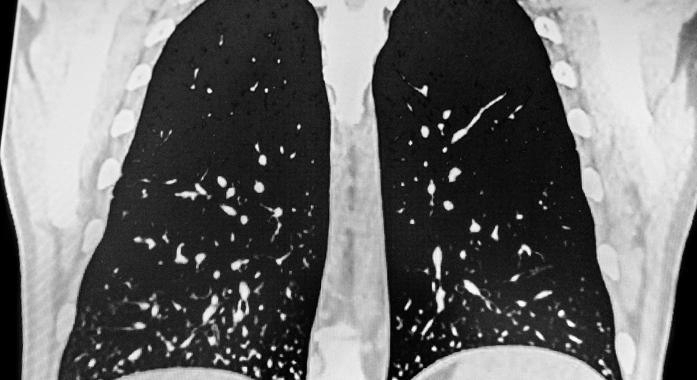

A hisztoplazmózis egy gombafertőzés kapcsán kialakult kórkép, melyet a Histoplasma capsulatum nevű kórokozó okoz.